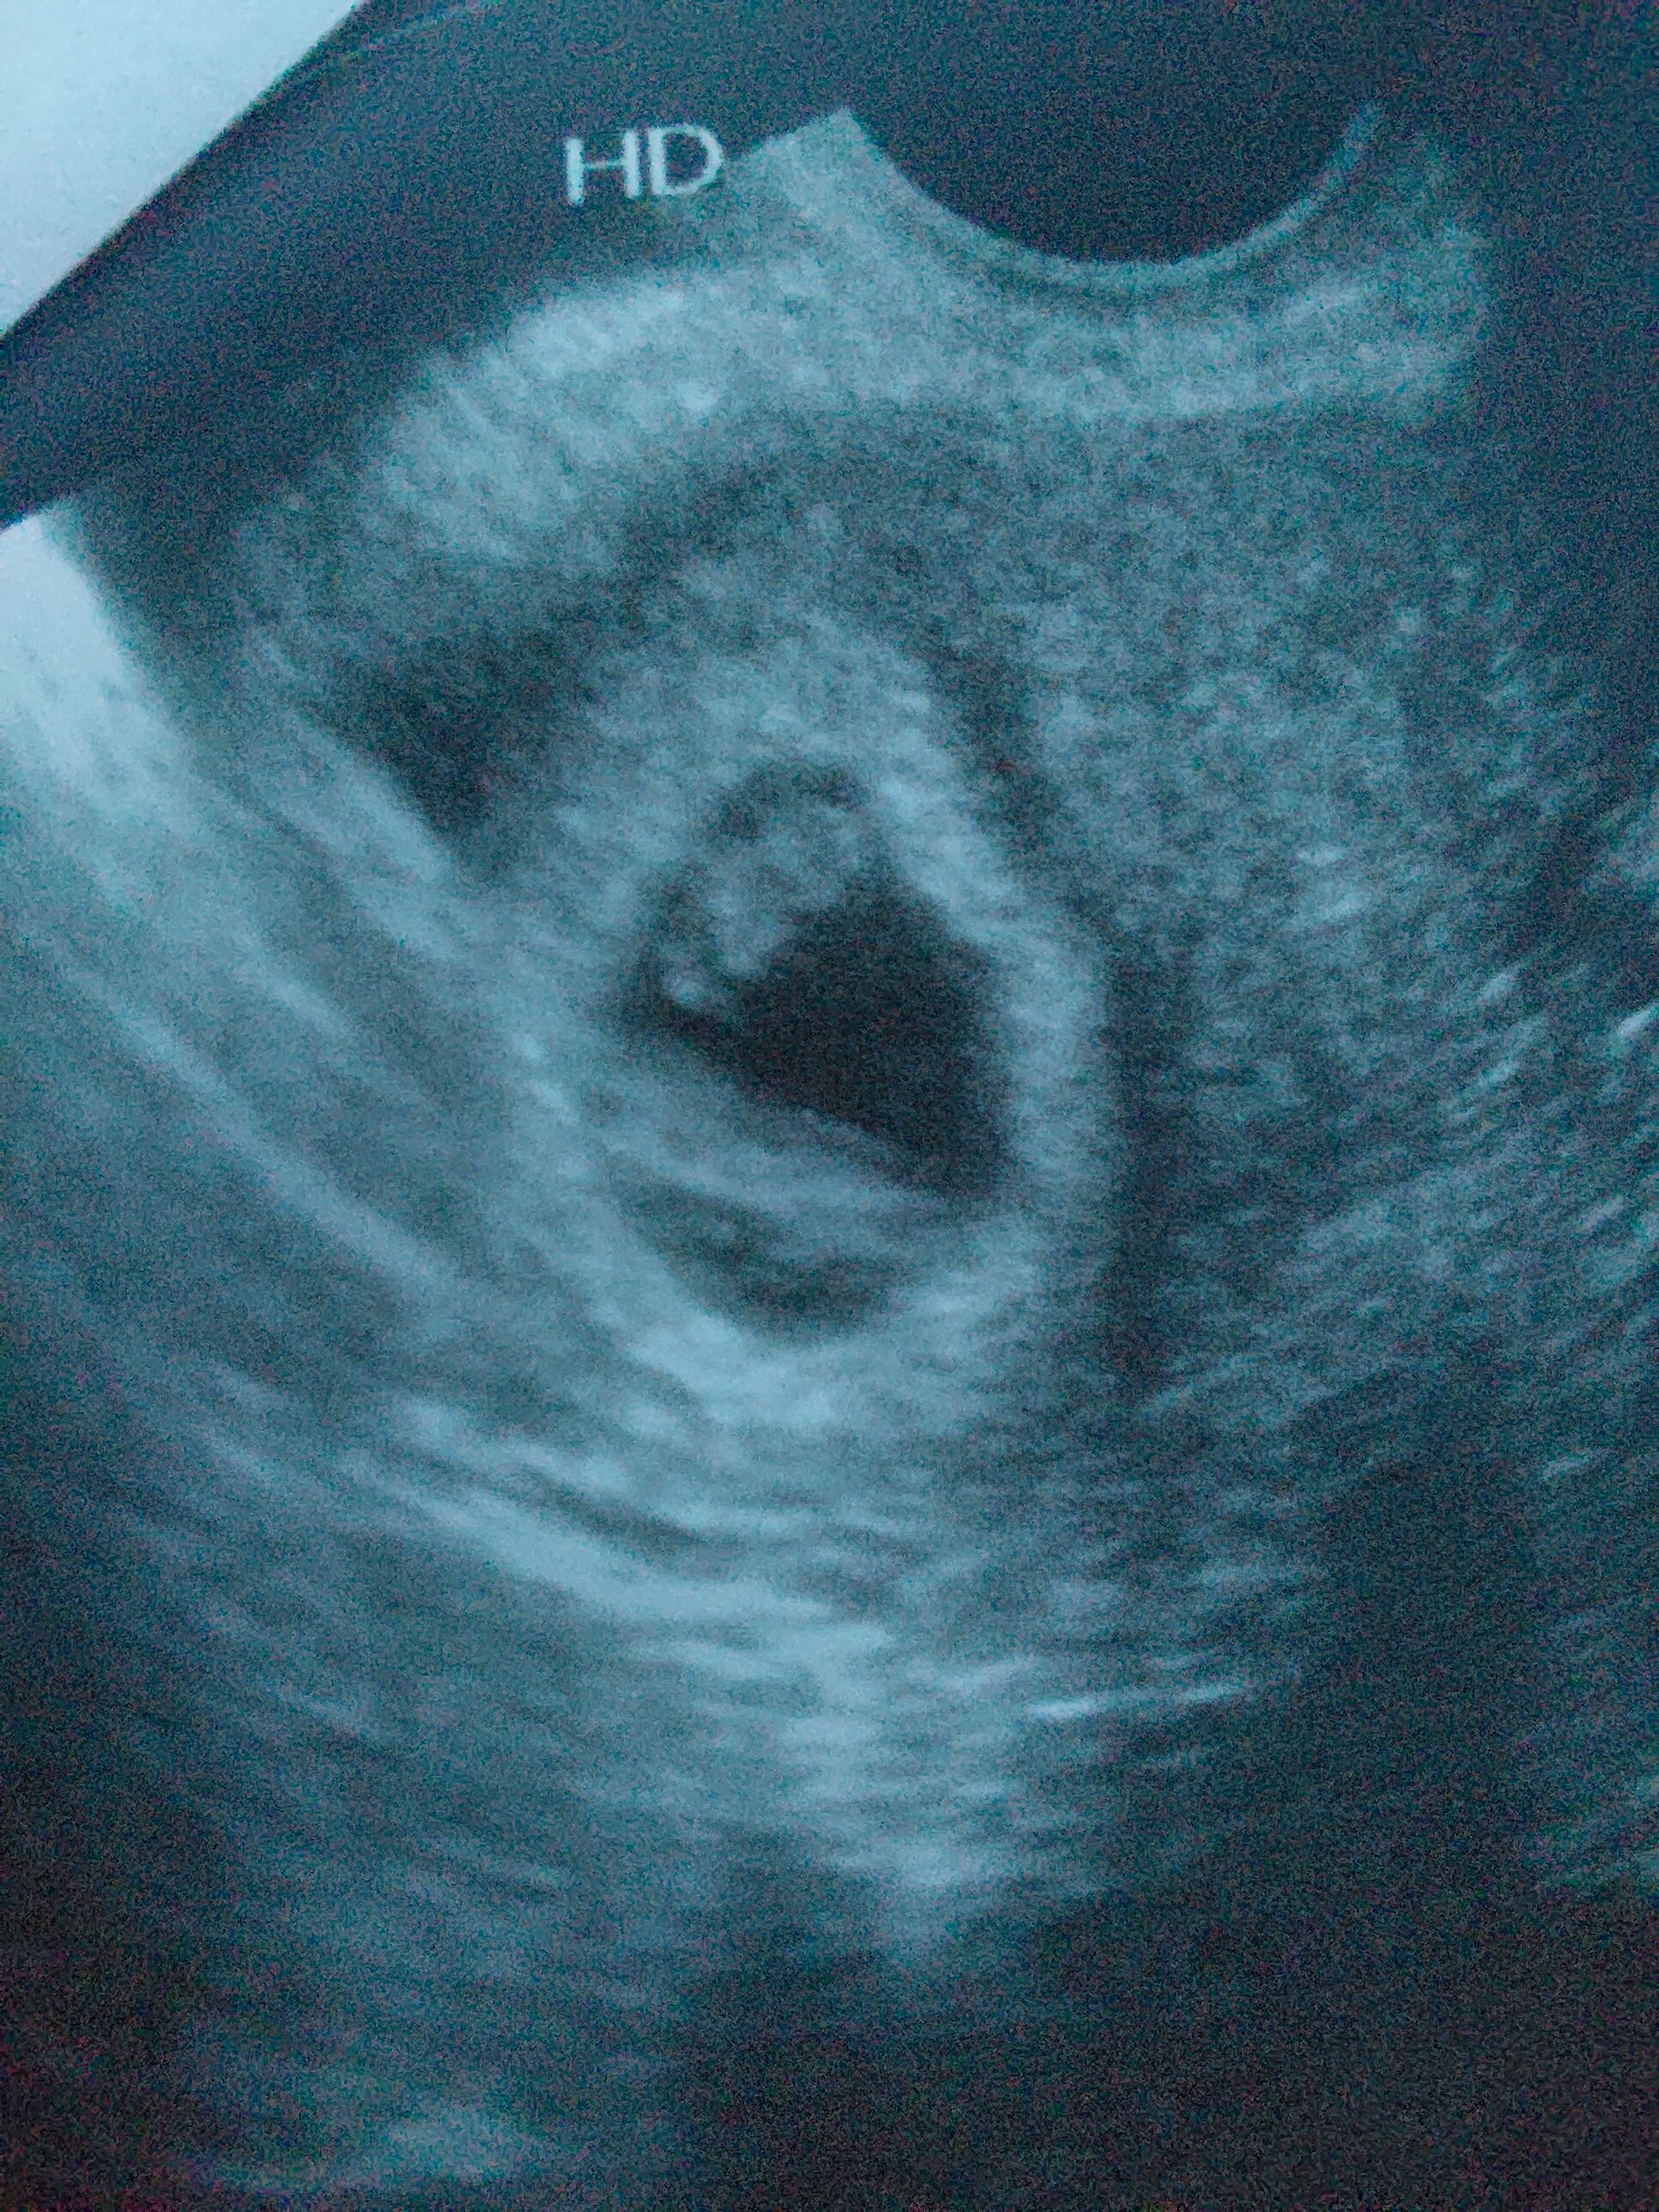

Wszystko jest dobrze! Serduszko bije, zarodek coraz większy ❤ z USG 6+5! (Czyli jeden dzien mniej niz z poprzedniego usg)

I zdjęcie 🥰

• 20230119_162533.jpg

20230119_162533.jpg

1,2 MB · Wyświetleń: 87